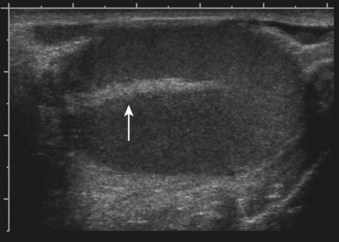

The glandular elements of the prostate have been divided into discrete zones, distinguished by the location of their ducts in the urethra, by their differing pathologic lesions, and, in some cases, by their embryologic origin (see Fig. 2–36). These zones can be demonstrated clearly with transrectal ultrasonography (Fig 2–39). At the angle dividing the preprostatic and prostatic urethra, the ducts of the transition zone arise and pass beneath the preprostatic sphincter to travel on its lateral and posterior sides. Normally, the transition zone accounts for 5% to 10% of the glandular tissue of the prostate. A discrete fibromuscular band of tissue separates the transition zone from the remaining glandular compartments and may be visualized at transrectal ultrasonography of the prostate. The transition zone commonly gives rise to benign prostatic hypertrophy, which expands to compress the fibromuscular band into a surgical capsule seen at enucleation of an adenoma. It is estimated that 20% of adenocarcinomas of the prostate originate in this zone.

Figure 2–39 Transrectal ultrasound of the prostate demonstrating the 1, peripheral zone and 2, transition zone.